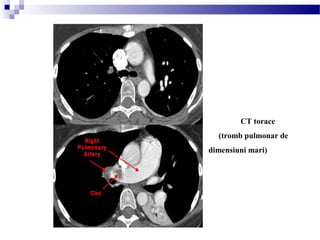

CT torace

(tromb pulmonar de

dimensiuni mari)

defect mare de umplere (sageată) reprezentând trombi la nivelul

arterelor pulmonare principale